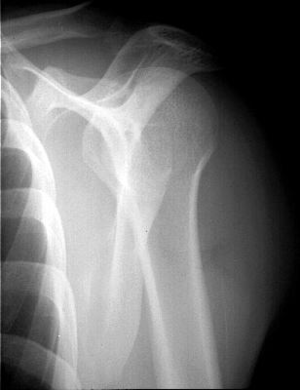

The views that should be included in the workup are a true anteroposterior view (grashey view), internal and external rotation view, a scapular Y view, and a Bernageau view. Posterior dislocation is missed initially on posteroanterior radiographs in 50% of cases, as the humeral head appears to be almost normally aligned with the glenoid.

On anteroposterior view, an overlap of the head in relationship to the glenoid can be observed (trough line sign, loss of the normal half-moon overlap sign, Figure 15). Moreover, an internally rotated humeral head gives a rounded appearance, which is called the lightbulb sign. Furthermore, the rim sign is defined as the space between the anterior glenoid rim and the humeral head being > 6 mm indicating a widened glenohumeral space (Figure 16).[18]